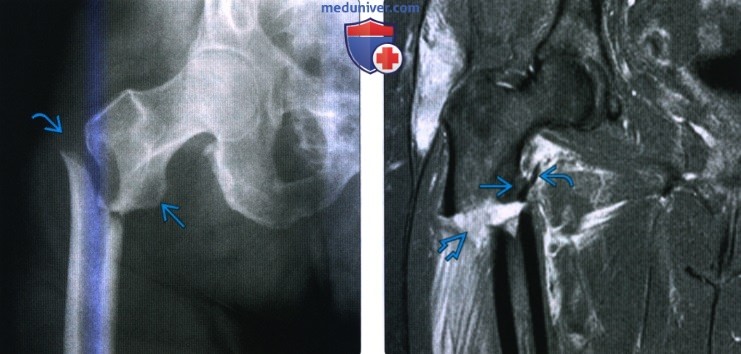

Классификация переломов диафиза бедренной кости: Иллюстрации и информация